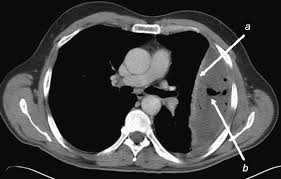

Parapneumonic Effusion Loculated Radiology Case Radiopaedia Org

Parapneumonic Effusion Loculated Radiology Case Radiopaedia Org from prod-images-static.radiopaedia.org